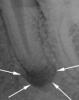

Nicholas Опубликовано 20 сентября, 2013 Автор Поделиться Опубликовано 20 сентября, 2013 (изменено) Без снимков тема будет закрыта... а вот теперь можете закрывать тему, т.к. после того как заменили пломбу на след день пол лица распухло сделали наконец то снимок на котором четко видно ПЕРИОДОНТИТ! о котором я твердил врачу, но тем не менее без всяких снимков мне залепили зуб и отправили домой.в итоге, зуб был удален, а я кушаю антибиотики вместо еды... Изменено 20 сентября, 2013 пользователем Nicholas Ссылка на комментарий

x3m Опубликовано 20 сентября, 2013 Поделиться Опубликовано 20 сентября, 2013 в итоге, зуб был удален,м-да...а по снимку - вроде вполне лечибельно... Ссылка на комментарий

Nicholas Опубликовано 22 сентября, 2013 Автор Поделиться Опубликовано 22 сентября, 2013 (изменено) Коронка была почти полностью разрушена, стоял штифт и все было замазано огромной пломбой ниже уровня десны. Возможно док посчитал что не стоит заморачиваться, не его же зуб! В общем зуб мне запортачили судя по всему, потому как когда мне снимки скинули там не было снимка зуба после того как воспалилось все, они его удалили сразу, этот я делал в другой клинике. Вот кстати снимок сразу после работы над каналом, не вижу ничего страшного хоть и не доктор, почему потом так сильно все воспалилось загадка... В общем что теперь сделаешь... Теперь вопрос в следующем, если я решу на место этого зуба имплант поставить сколько времени мне надо ждать после удаления чтобы все зарасло и было готово для установки импланта???? Изменено 22 сентября, 2013 пользователем Nicholas Ссылка на комментарий